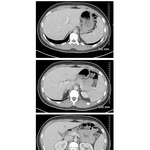

• Abdominal Scans: Axial CT Images

326. Abdominal Scans: Axial CT Images